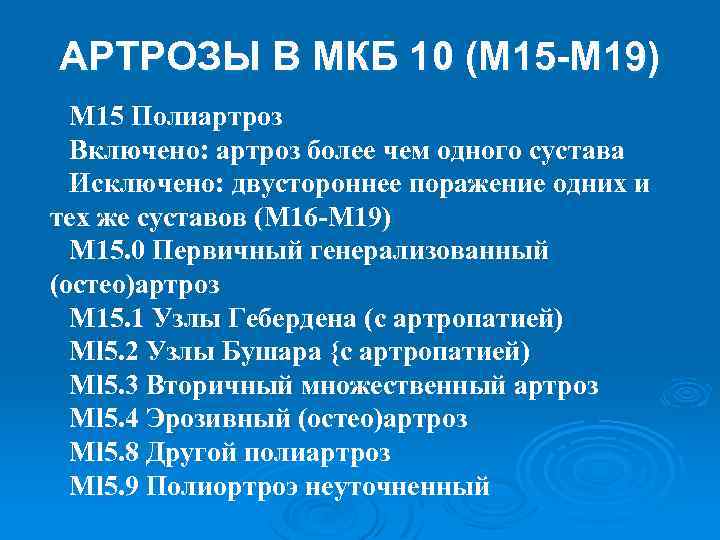

Код мкб 10 атерома головы

Код мкб 10 атерома головы 109 фото